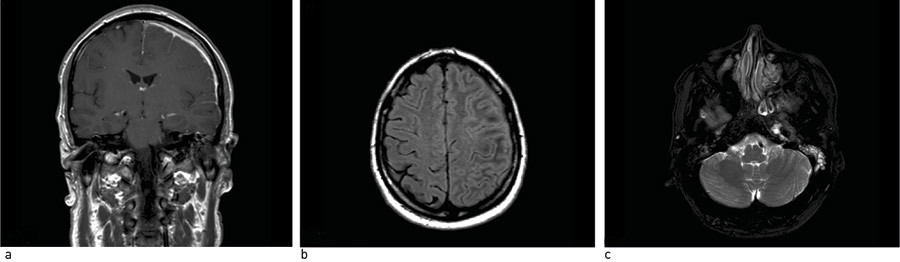

After his return to Norway, three weeks after the onset of symptoms, the patient developed blurred vision in the right eye, and was hospitalised at the University Hospital of North Norway. On admission he was in a slightly reduced general condition. The patient had significantly reduced right eye vision, tinnitus in the left ear and slight dysarthria. Extensive blood screening showed a sedimentation rate of 74 mm/h (2 – 12 mm/h), CRP of 83 mg/l (< 5 mg/l) and slightly elevated c-ANCA (S-Anti-PR3) of 12 U/ml (negative: 0 – 10 U/ml, positive: 11 – 530 U/ml), but otherwise normal findings. Spinal fluid analysis revealed slight pleocytosis with white blood cells of 29 · 10⁶/l (< 5 · 10⁶/l) and total protein of 686 mg/1 (< 500 mg/l). The opening pressure of the lumbar puncture was normal. The ophthalmologist’s conclusion was infarction of the right optic nerve. The ear, nose throat specialist found crust formation in the left nasal cavity, and there was suspected leakage of cerebrospinal fluid from the left ear. No infectious agent was detected in any of the body fluids (blood, cerebrospinal fluid, ear secretion, nasopharynx or urine). MRI of the head revealed a fluid rim with swelling and contrast enhancement in the meninges over the left hemisphere and fluid in the mastoid area on the left side (Figs 1 a – c). This was interpreted as probable meningeal effusion. The conclusion was bacterial meningitis, and the patient was put on antibiotics.

Figure 1  MRI caput: a) T1 sequence with contrast. Swelling of the meninges over the left hemisphere with contrast…

Figure 1 MRI caput: a) T1 sequence with contrast. Swelling of the meninges over the left hemisphere with contrast enhancement. b) T2 sequence. Thickened meninges on the left side and signal changes in adjacent cerebral parenchyma. c) T2 sequence, FLAIR. Fluid in the mastoid area, around the internal carotid artery and the jugular vein at the base of the skull on the left side.

The patient had also complained of numbness corresponding to the ophthalmic branch of the trigeminal nerve over the affected eye. The headache was now located mainly in the right temple region up towards the forehead. A further MRI of the head and re-examination of the previous scan retrospectively revealed fluid and soft-tissue congestion around the left internal carotid artery and the jugular vein below the skull base (Fig. 1c). The condition was interpreted as being Wegener’s granulamatosis, with weakly positive c-ANCA, thickening of the mucous membrane in the sinuses, small nodular opacities in the lungs, external ophthalmoplegia with affection of several eye muscles and numbness of the forehead – even though no biopsy findings confirmed the diagnosis. The patient was transferred to the Department of Rheumatology. Because of the severity of the disease, he was treated with intravenous cyclophosphamide for six months with plans for a transition to methotrexate as maintenance treatment. However, at the evaluation after the treatment with cyclophosphamide, a further MRI head scan showed increased thickness of the meninges, and the patient was given rituximab. He has responded well to this treatment. Up to now, three rounds of therapy have been administered. The disease is in remission, the patient is free of symptoms and back in full-time work.